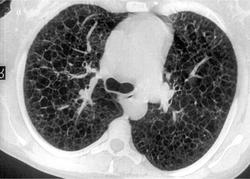

Типичный пример патологии при которой основным патерном являются кисты - :

материал взят со статьи Dr.Mario

http://www.radiomed.ru/publications/luchevaya-diagnostika-diffuznykh-interstitsialnykh-zabolevanii-legkikh-dizl-obshchie--0

Лимфангиомиоматоз.

Из архива AFIP. Лимфангиолейомиоматоз.